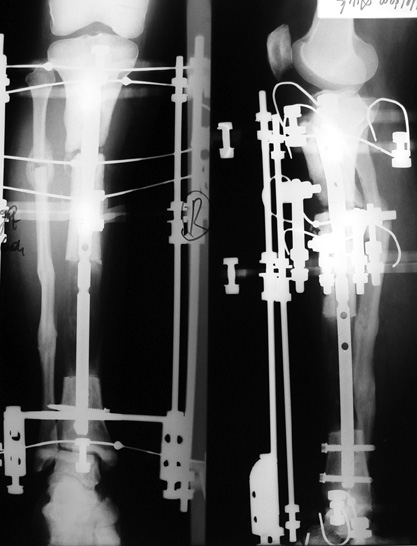

The duration of external fixation (external fixation index) depends on the amount of distraction required, and the extremity is prone to complications during this period. After the distraction phase is completed, the external fixator remains in place during the consolidation phase, which lasts twice as long as the distraction phase; but this period is hardly tolerated. If the external fixator is removed before sufficient consolidation is achieved, fractures, deformity and shortness will be the result. In our department, ‘lenghthening over nail’ method is used in order to decrease the external fixation index and increase patient comfort and activity level. In this method, the intramedullary nail is statically locked after the completion of the distraction phase, and external fixator is removed. The extremity is stabilized by the intramedullary nail during consolidation phase. In this way, complications due to long external fixation index or early removal of the external fixator are avoided.